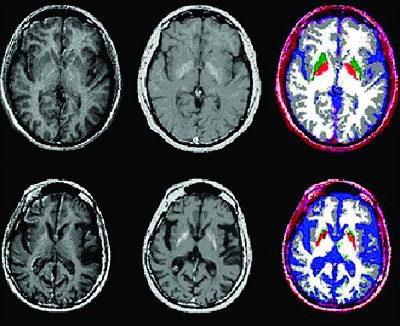

| Graph showing positive linear correlation between decline in F-18 FDG uptake in caudate (above A; r2 = 0.34, p = 0.003) or putamen (below B, r2 = 0.44, p = 0.0001) and estimate number of years until Huntington's disease onset in presymptomatic gene-positive subjects. Positive linear correlation was found between decreased striatal F-18 FDG uptake and expected years until onset. Andrea Ciarmiello, Milena Cannella, Secondo Lastoria, Maria Simonelli, Luigi Frati, David C. Rubinsztein, and Ferdinando Squitieri, "Brain White-Matter Volume Loss and Glucose Hypometabolism Precede the Clinical Symptoms of Huntington's Disease" (J Nucl Med 2006; 47;215-222, Figures 2 and 5). |